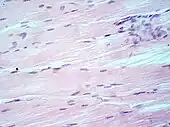

Main types of staining seen on H&E stain.

The structures do not have to be acidic or basic to be called basophilic and eosinophilic; the terminology is based on the affinity of cellular components for the dyes. Other colors, e.g. yellow and brown, can be present in the sample; they are caused by intrinsic pigments such as melanin. Basal laminae need to be stained by PAS stain or some silver stains, if they have to be well visible. Reticular fibers also require silver stain. Hydrophobic structures also tend to remain clear; these are usually rich in fats, e.g. adipocytes, myelin around neuron axons, and Golgi apparatus membranes.

Examples of H&E stained tissues